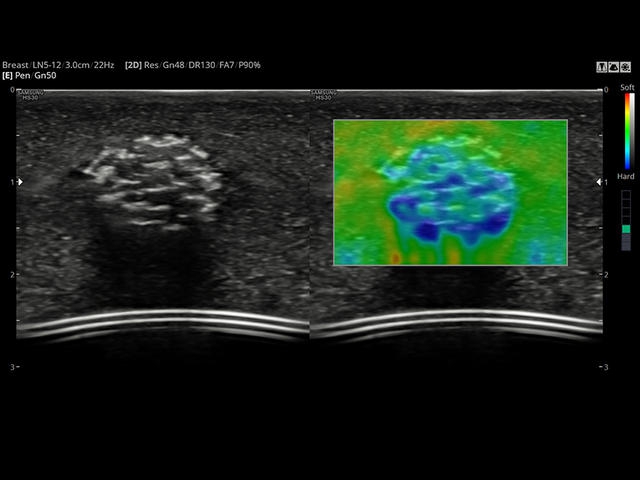

- Модуль Elastoscan - программы эластографии (качественная оценка) для исследований щитовидной железы, молочной железы у женщин и предстательной железы у мужчин.